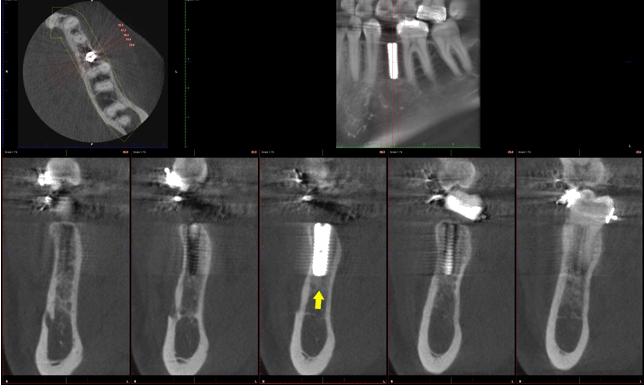

Figure 4: Post-surgical dental implant assessment (four months). Cone beam computed tomography images represent an axial (top) and cross-sectional slices (lower) of the implant area (location at area of extracted tooth #35). The cross-sectional slices show the successful positioning of dental implant relative to buccal and palatal cortical plates (yellow arrow; location at area of extracted tooth #35).